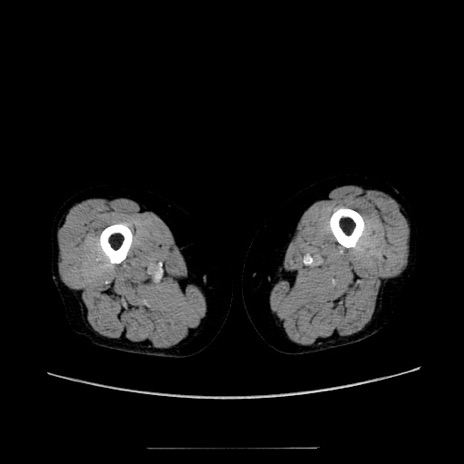

症例5(横断像)

【症例】70歳代女性

【主訴】お腹が張る

【現病歴】1週間くらい前から腹部膨満の自覚あり。昨日夜から増悪したため、本日救急外来受診。

【身体所見】意識清明、BT 36.5℃、BP 165/106mmHg、HR 80bpm、SpO2 98%、腹部:膨満、軟、自発痛・圧痛なし、触診にて不快感あり、腸蠕動音:減弱

【データ】WBC 12600、CRP 1.04